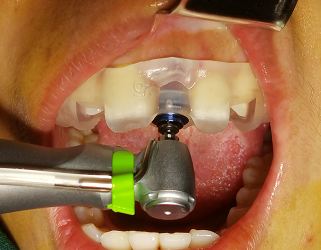

近日,我院口腔科伍栋副主任医师团队再次为一名患者完成数字化精准种植即刻修复负荷固定义齿技术,实现了患者“当天种牙、当天吃肉”的愿望。据悉,此项种植技术是我院口腔科成功...